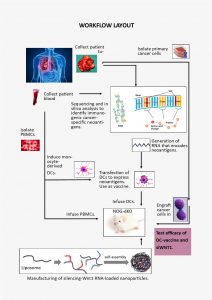

Παντατοσάκη Ευαγγελία, Επιστημονικός Υπεύθυνος του ερευνητικού έργου με τίτλο: «Μηχανική γονιδιακών νανοσωματιδίων: Υπολογιστική μελέτη με σκοπό στοχευμένες αντικαρκινικές θεραπείες»

Η αντιμετώπιση του καρκίνου μέσω της συμβατικής χημειοθεραπείας περιλαμβάνει τη χορήγηση κυτταροτοξικών φαρμάκων τα οποία καταστρέφουν αδιακρίτως καρκινικά και υγιή κύτταρα προκαλώντας σοβαρότατες παρενέργειες. Επίσης, οι εναλλακτικά χρησιμοποιούμενες στοχευμένες και ανοσολογικές θεραπείες έχουν περιορισμένα θετικά αποτελέσματα και λειτουργούν σε πολύ μικρό εύρος καρκίνων. Μια από τις πλέον υποσχόμενες μορφές στοχευμένης θεραπείας στις μέρες μας περιλαμβάνει ειδικά σχεδιασμένα γονιδιακά φάρμακα, τα οποία στοχεύουν επιλεκτικά τα καρκινικά κύτταρα, αφήνοντας ταυτόχρονα τα υγιή κύτταρα ανέγγιχτα.